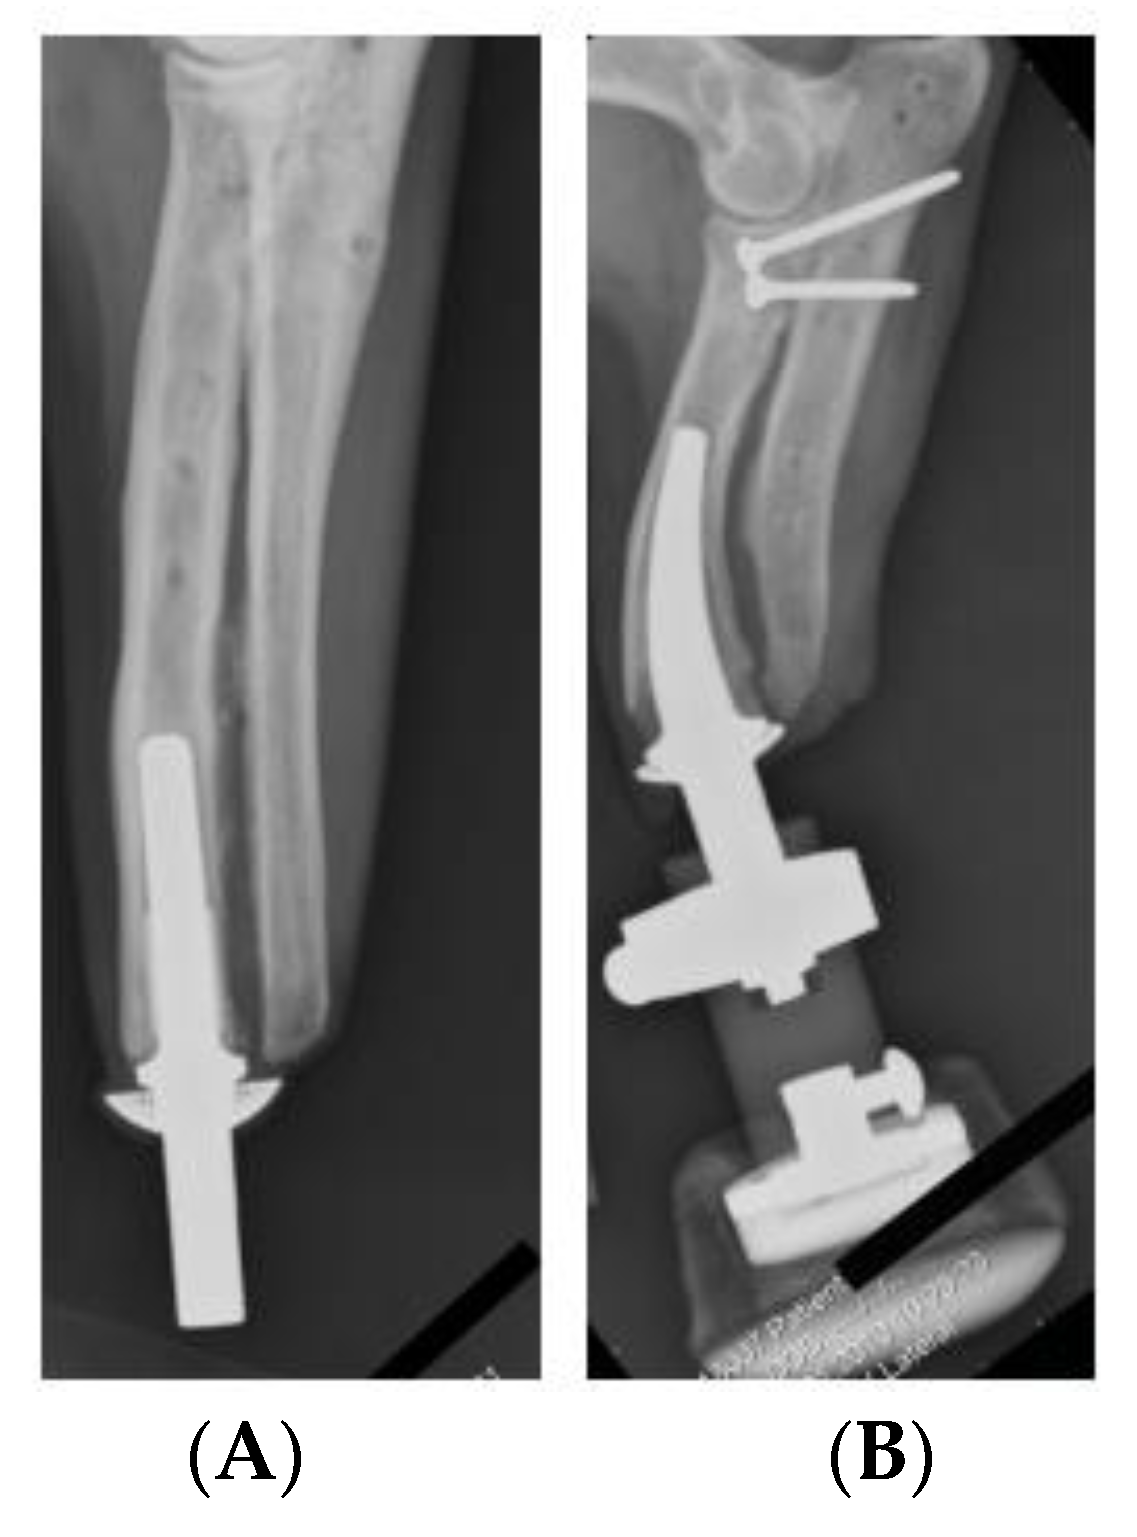

Other direct skeletal prosthetics are available for use such as Osseointegrated Prostheses for the Rehabilitation of Amputees, OPRA. This system involves screwing into the bone cavity which increases the residual σ all along the anchor. This system works because it increases the user’s hip flexibility and extension in comparison to traditional socket interfaces. However, over time it was recorded that pain was detected due to the build-up of residual σ [14]. The ITAP is not only suited to use in humans but it has had clinical trial in canines. Noel Fitzpatrick et al. studied the procedure for installation and use in four separate canines. The study identified that all subjects’ quality of life improved due to the prosthetic attachment. However, canines 1–3 were euthanized due to metastatic disease spreading throughout the body; it was unclear if this was related to the ITAP [15]. As the ITAP can be fitted for different purposes and species, bespoke parts can be produced. This is extremely useful as the properties of bone vary as well as the length of the remaining bone after amputation, see Figure 1 and Figure 2. Bone shape and modelling can be recorded by using Computed Tomography (CT) scanning. This creates a need for design iterations to model and build an ITAP that suits the individual’s lifestyle. In this process it is essential to design a build that does not over engineer the forces acting upon the leg. Failure to work in this design constraint could cause near fatal damage to the user resulting in further amputation or loss of life. This is due to the failure of the anchor supporting the ITAP and the potential rupturing of arteries and veins surrounding the localized area of the prosthetic. The work of Sullivan et al. concluded that the use of direct skeleton attachments for prosthetics increases the user’s quality of life and the function of the prosthetic limb. Comfort also increased due to the lack of sores developing on the stump. This is because there is no contact between the stump of the limb and the prosthetic sock fitted over the top. However, the reports concluded that aspects of the development of the ITAP needed further advancement because the “trans-femoral amputee” case needs extensive review before it becomes a common clinical procedure for prosthetic rehabilitation [16]. It has been identified by Bird et al., that the initial area of failure and high σ concentration of the ITAP is located at the root of the ITAP [13]. The results of the study identified that a single safety notch was not enough for the ITAP to be suitable for use. This is because the strength of the Ti used for the ITAP is greater than the bone, so the bone would fail before the ITAP, resulting in damage to the user. Thus, it is identified that a comparable σ between bone and the ITAP at the point of insertion is needed for successful development of the product. This is categorized as designing in failure for success.

Figure 2. (A) Canine prosthetic ITAP embedded into its front left leg. (B) A Canine bespoke ITAP embedded into its front right leg [15].